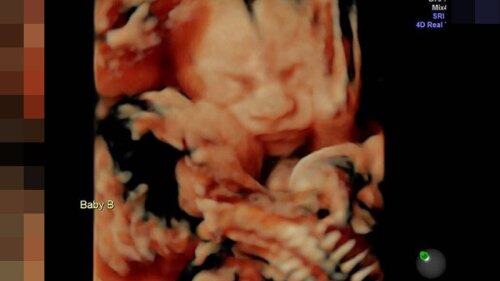

Esta podría ser la foto de un ultrasonido más tierna en todo el mundo.